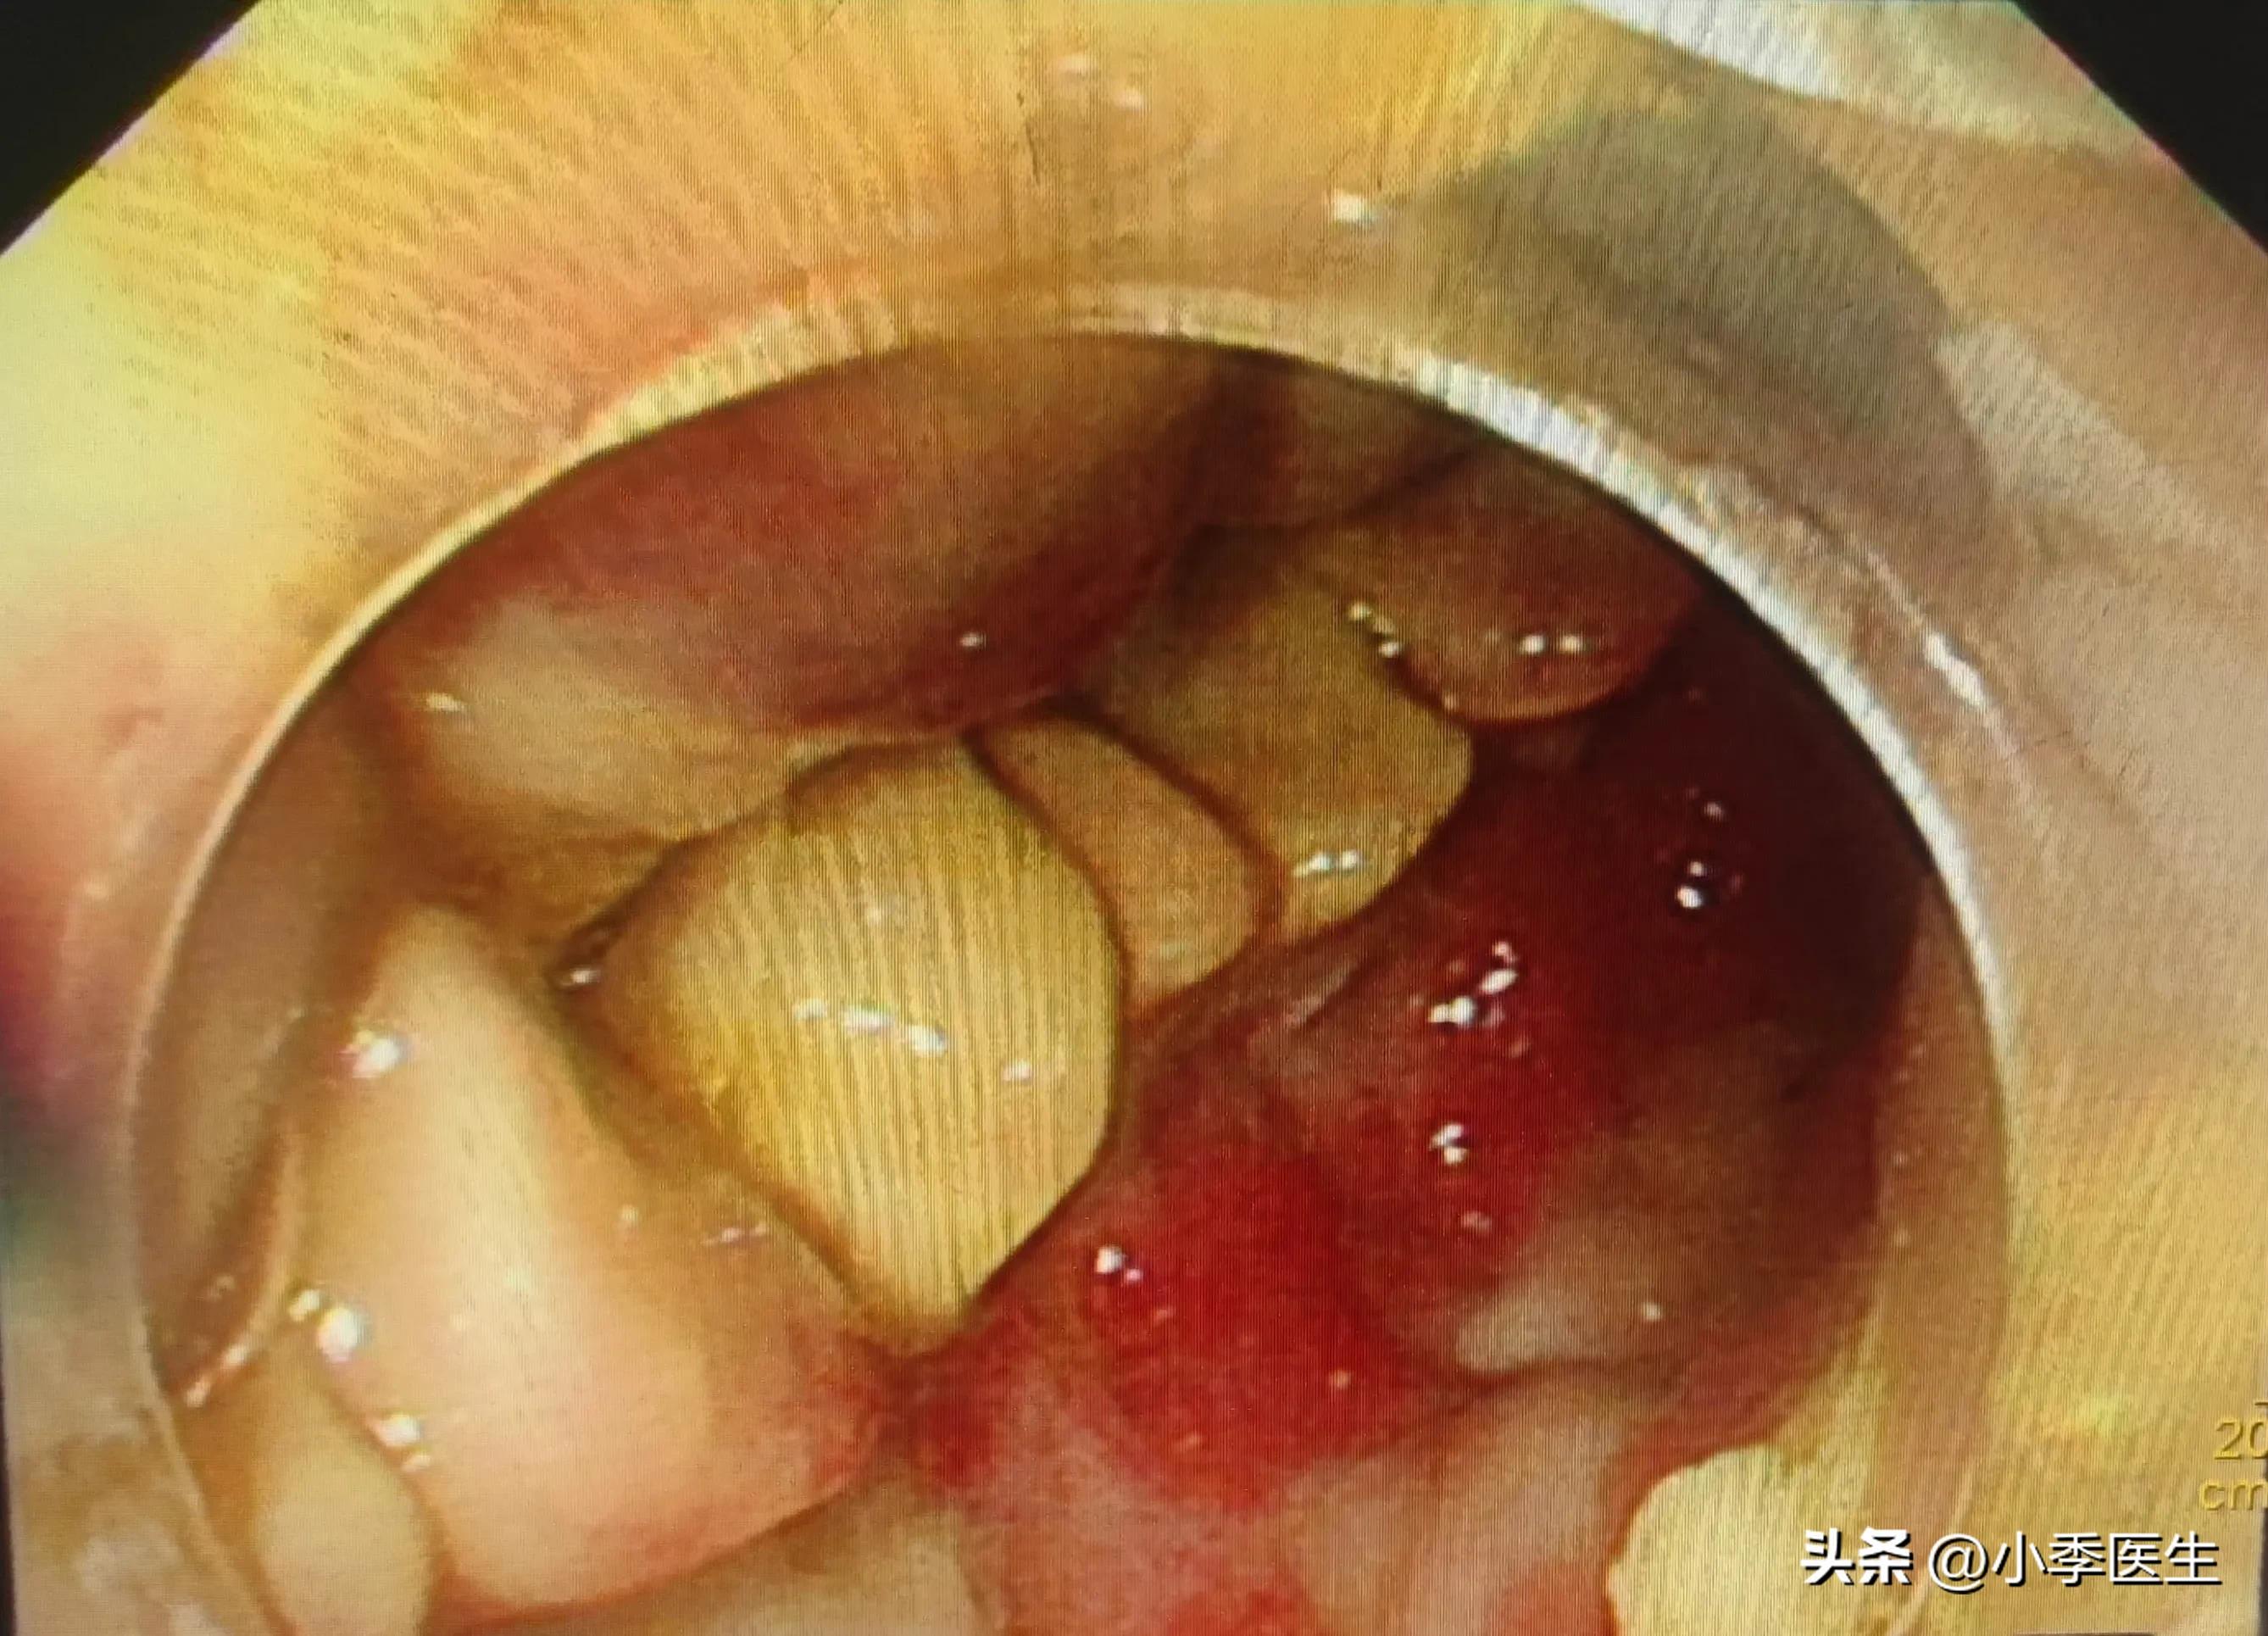

肠镜下所见